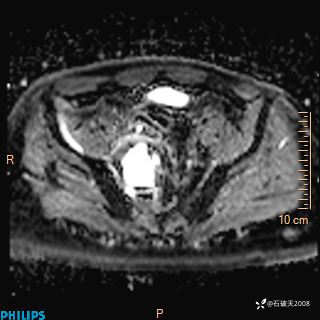

2023年3月份MRI影像

增强轴位